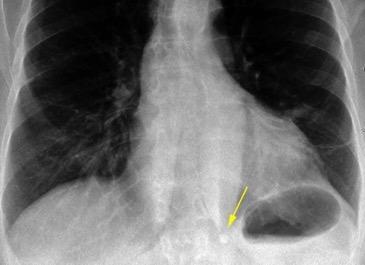

Shock hipovolémico tras puñalada.

Hemotórax

Coágulo centinela

Pedrosa I et al. Intercostal artery injury manifested by a sentinel pleural clot. Emerg Radiol 2001